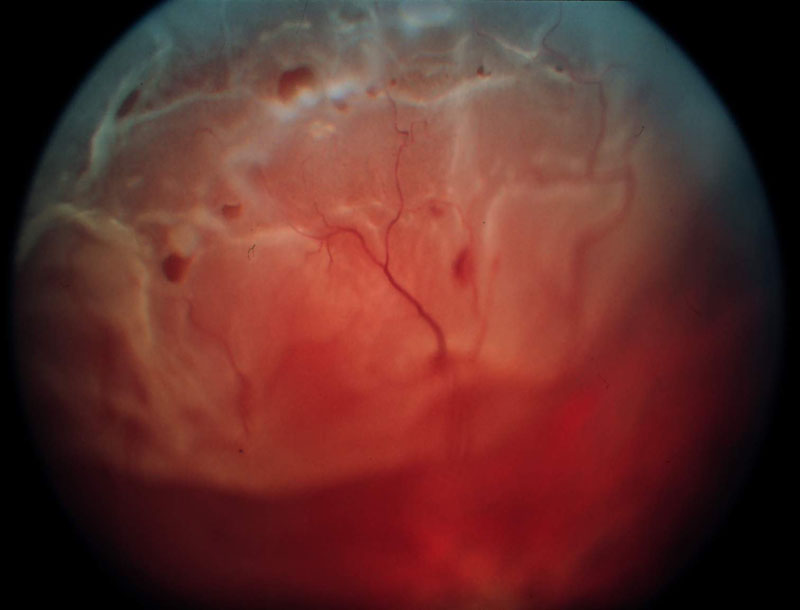

1. ábra

1. ábra Óriás szakadás következtében kialakult ablatio retinae szemfenéki képe. A QuadrAsphericus lencse széle látószögének köszönhetően gyorsan áttekinthetjük a fundus egészét. Jól érzékelhető az óriás szakadás kötényszerűen előrehajló hátsó széle.